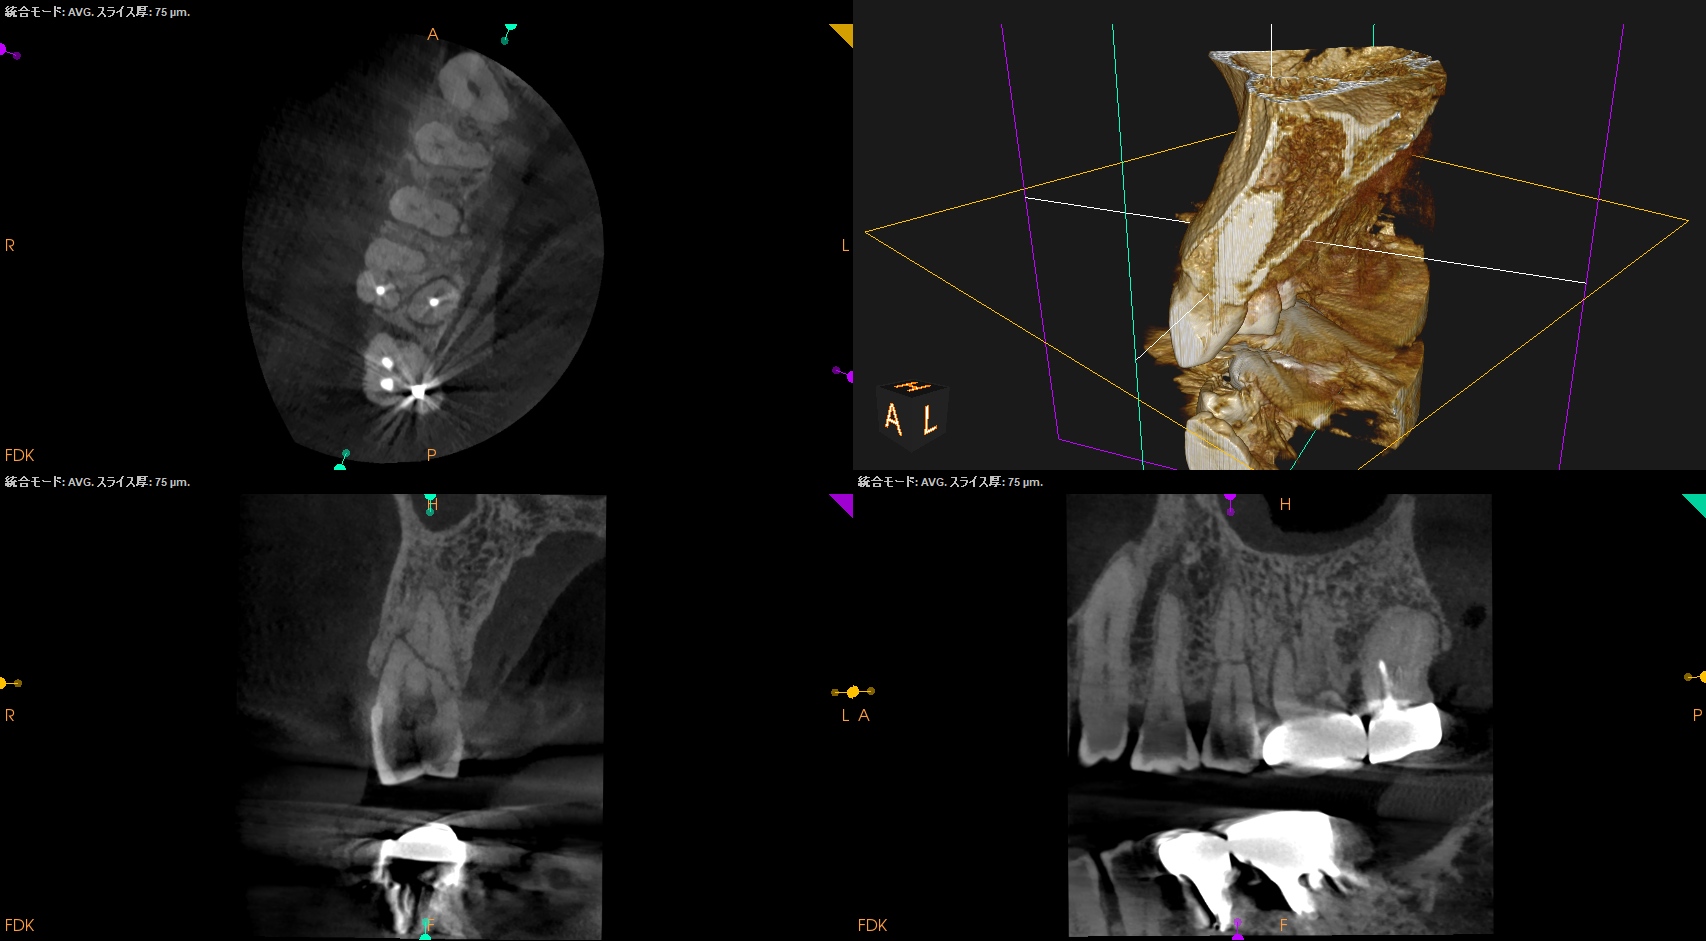

CBCT(2024.10.28)

#4

歯根の中央で水平に破断している。

ここで重要なことは破折片の口蓋側寄りの歯根には病変がないということだ。

ということは…

そこは根管治療が不要である。